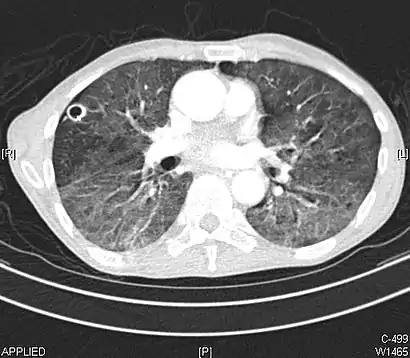

High-resolution CT image showing ground-glass opacities in the periphery of both lungs in a patient with COVID-19 (red arrows). The adjacent normal lung tissue with lower attenuation appears as darker areas.

Ground-glass opacity is among the most common imaging findings in patients with confirmed COVID-19.[16][17] One systematic review found that among patients with COVID-19 and abnormal lung findings on CT, greater than 80% had GGOs, with greater than 50% having mixed GGOs and consolidation.[16] GGOs with mixed consolidation has most often been found in elderly populations.[18] Several studies have described a pattern among initial, intermediate, and hospital discharge imaging findings in the disease course of COVID-19. Most commonly, initial CT imaging reveals bilateral GGOs at the periphery of the lungs. During initial stages, this is most often found in the lower lobes, although involvement of the upper lobes and right middle lobe has also been reported early in the disease course.[16][18] This is in contrast to the two similar coronaviruses, SARS and MERS, which more commonly involve only one lung on initial imaging.[19][20] As the COVID-19 infection progresses, GGOs typically become more diffuse and often progress to consolidation.[11][18] This is sometimes accompanied by the development of a crazy paving pattern and interlobular septal thickening.[18] In many cases the most severe pulmonary CT abnormalities occurred within 2 weeks after symptoms began.[17] At this point, many individuals begin showing resolution of consolidation and GGOs as symptoms improve. However, some patients have worsening symptoms and imaging findings, with further increase in septal thickening, GGOs, and consolidation. These patients may develop lung "white-out" with progression to acute respiratory distress syndrome (ARDS) requiring treatment escalation.[17][21]